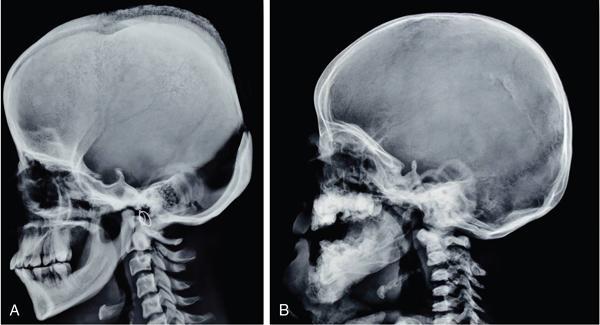

MISCELLANEOUS PAEDIATRIC RADIOGRAPHY – TECHNIQUES AND INTERPRETATION: SKELETAL SURVEY Padma V. Badhe The skeletal survey, generally performed in children, is a set of radiographs done in order to evaluate the entire skeleton. A skeletal survey, commonly used to evaluate skeletal dysplasias, acquired metabolic disorders and suspected child abuse, is still the key radiological investigation for the same. Hence, an explicit understanding of the technique along with the common disorders forms the basis of making a diagnosis in these paediatric pathologies. A skeletal survey is done for various skeletal dysplasias, non-accidental injury (battered baby syndrome) and suspected child abuse. It can also be done in cases of metabolic bone diseases, disseminated infections, multiple myeloma, eosinophilic granuloma. It is also used in evaluation of metastatic bone diseases and polyarticular arthropathy. Orthogonal views of the skull, spine, pelvis and one extremity are taken, preferable in standing position. For preterm babies/newborns, AP and lateral views of babygram may be taken. Projections: For skeletal dysplasias: Additional views: Both extremities may be taken if epiphyseal abnormalities and limb asymmetry is present. Focused views for specific pathologies may be taken. When a diagnosis remains uncertain, 1 year follow up is usually recommended. For preterm babies/newborns: AP and lateral views of babygram may be taken with additional specific views for extremities. For suspected non-accidental injury (NAI): AP and oblique view of chest is taken for better evaluation of the ribs. AP view of abdomen with pelvis. Both upper and lower limbs are evaluated. In lower limbs, two projections in AP and lateral (one with both femur including hip and knee joints; and another for foot and ankle) is taken. AP and lateral views of whole spine, skull. Oblique view of hands. A babygram should be avoided in cases of NAI, as subtle fractures are easily missed. Proper legal documentation while taking the views is very important and ideally two health care professionals must be present. For metabolic disorders: entire skeletal survey is usually not required. Specific views of hands, knees and spine may be taken with additional views depending on the suspected pathology. Centring point: Varies according to the part being examined. Angulation, collimation and orientation: Varies according to the part being examined. Images must be well collimated to obtain lower radiation dose. Detector size: Varies according to the part being examined: 8″ × 10″, 10″ × 12″, 11″ × 14″. Exposure: Ideally high kVp images are taken to reduce radiation dose. But in suspected NAI, low kVp/high mA images are recommended to better demonstrate findings. SID (Source Image Distance):100 cm Grid: Grids are not routinely used to image spine, pelvis, skull and abdomen in children. Radiation dosage: 0.3–3 mSv Essential image characteristics: Adequate spatial resolution, high signal to noise ratio, low kVp (50–70) for high contrast should be done. Excellent bone and soft tissue details are required. The presentation of skeletal dysplasia can range anywhere from minimal stunting of growth and bowing of limbs to severe dwarfism and multiple fractures. Knowledge of the commonly encountered dysplasias with an approach to arrive at a diagnosis is vital in any Radiologist’s practice The following flow chart summarizes the classification of important skeletal dysplasia: The following table summarizes the various dysplasias affecting the axial skeleton: TABLE 7.5.1.1 The following flow chart summarizes the working approach to skeletal dysplasias: Osteopetrosis (Albers-Schonberg disease/Marble bone disease) (Fig 7.5.1.1): Osteopetrosis clinically presents with anaemia/thrombocytopenia or cranial nerve compression. Radiological features include generalized increase in bone density with loss of medullary space. However, cortico-medullary appreciation with cortical thinning is also rarely seen. Bone within bone appearance with Erlenmeyer flask deformity is also noted. Pyknodysostosis (Figs. 7.5.1.2 and 7.5.1.3): patient presents with short stature. Unlike osteopetrosis, there is no anaemia. Radiographs show generalized increase in bone density with preserved medullary canal. There is mandibular hypoplasia with obtuse angle. Acro-osteolysis is also a feature. Dental caries with osteomyelitis of the jaw may be seen. Sclerosing dysplasia presenting as wavy undulating new bone formation. Usually monomelic, lower limb and along one side. The classic appearance is described as Dripping candle Wax sign. It is a Sclerosing dysplasia with radiological features of symmetric juxta-articular involvement in epimetaphyseal region. They are 1–10 mm in diameter and uniform in size. No metabolic activity is seen on bone scans. This skeletal dysplasia shows diffuse decrease in bone density with paper-thin cortex. Fractures heal in normal time but shows callus with poorly cellular matrix. Wormian bones and enlarged sinuses may be seen. Codfish vertebra (Biconcave vertebra) may be seen. Metaphyseal corner fractures are not seen in osteogenesis imperfecta that helps to differentiate it from battered baby syndrome. There are four types of OI out of which type one is most common (Figs. 7.5.1.6 and 7.5.1.7). The radiological features of MPS include Osteopenia and Universal platyspondyly. The intervertebral disc spaces are maintained. Proximal pointed metacarpals is an important radiological finding. Hurler’s syndrome show anteroinferior beaking with short and wide metacarpals. Varus deformity of humerus is characteristically seen in Hurler’s syndrome (Fig. 7.5.1.8). Mental retardation & corneal clouding is seen in Hurler’s syndrome whereas these Hunter’s disease has normal intelligence with no corneal clouding. Morquio’s syndrome shows central beaking (Fig 7.5.1.9). This skeletal dysplasia shows normal bone density with rhizomelic limb shortening and normal trunk. Narrowing of spinal canal is classically seen with decrease in the Interpedicular distance caudally. Other radiological features include trident hand (separation of middle & third fingers), Champagne glass pelvis (short, flat ilia and small sciatic notch), bullet nose vertebra and overexpansion of skull with narrow foramen magnum (Fig. 7.5.1.10). This skeletal dysplasia is characterized by normal bone density with dwarfism and normal craniofacial skeleton. The interpedicular distance is normal. There is severe platyspondyly with anterior tonguing (disappears at older age). Other radiological features include increased disc space, short stubby metacarpals, small irregular epiphysis and widened metaphysis. Anterior tonguing is a feature of Pseudoachondroplasia. This form of skeletal dysplasia involves the spine and epiphyses (Fig. 7.5.1.11). There is normal bone density with rhizomelia. Spine and Pelvis can be involved. Premature osteoarthritis can be seen. The other characteristic features include Platyspondyly and small irregular epiphysis. There are two forms Spondyloepiphyseal dysplasia Congenital and Spondyloepiphyseal dysplasia Tarda. Spondyloepiphyseal dysplasia Congenita is Autosomal dominant and shows pear-shaped vertebrae. Spondyloepiphyseal dysplasia Tarda is X Linked recessive with heaped up vertebrae. It has two forms. The first form is Conradi Hunermann syndrome which is autosomal dominant characterized by asymmetric limb shortening with metaphyseal flaring (Fig. 7.5.1.12). The Autosomal recessive form is Fatal in first few years. Rickets: Rickets refers to deficient mineralization of the growth plate in the paediatric population due to deficiency of vitamin D. In an immature skeleton, there is abnormal mineralization at the zone of provisional calcification in the metaphysis due to osteoid deposition resulting in widening of the growth plate. The features of rickets include fraying, splaying and cupping (Fig. 7.5.1.13). Fraying denotes indistinct margins of the metaphysis whereas splaying denotes widening of metaphyseal ends. Term ‘Cupping’ is used for increased concavity of the metaphysis. These findings are typically seen involving areas of active growth (e.g. distal femur and proximal tibia in the knee) Bowing is a result of associated osteomalacia leading to weakening of weight-bearing lower limb bones. Other bone deformities such as genu valga, genu varum, protrusio acetabuli can also be seen. The lower ribs may also be drawn inwards inferiorly by the attachment of the diaphragm this is called Harrison’s sulcus. Scurvy: Scurvy is a result of dietary deficiency of Vitamin C (ascorbic acid). The classic presentation is that of a patient with an increased bleeding tendency and osteopenia with poor wound healing. Features of scurvy include generalized osteopenia with cortical thinning termed as ‘pencil-point’ cortex. Other radiological findings include the periosteal reaction due to subperiosteal haemorrhage. Expansion of the costochondral junctions occurs forming scorbutic rosary. Bleeding into the joint spaces may result in hemarthrosis. Circular, opaque radiologic shadow surrounding epiphyseal centres of ossification may result from bleeding (Wimberger ring sign) (Fig. 7.5.1.14). Frankel line may be seen. It represents dense zone of provisional calcification. Lucent metaphyseal band is seen underlying Frankel line called as Trümmerfeld zone. Metaphyseal spurs may be seen that result in cupping of the metaphysis (Pelkin spur). Pelkin fracture (metaphyseal corner fracture) can also be seen. Images obtained must be of good resolution with adequate bone and soft tissue details. Additional views: They have already been described in positioning. CT Brain in can be done in cases of NAI to look for subdural hematomas. A skeletal survey is the first-line imaging modality for evaluation of skeletal dysplasia, nonaccidental injury and metabolic bone diseases. The skeletal survey must be tailored according to the respective indication. It helps to characterize syndromic patterns in skeletal dysplasias, with evaluation of complications. In cases of diagnostic dilemmas, additional focused view and occasionally yearly follow-up is recommended. A high index of suspicion is needed in utilizing skeletal survey as a diagnostic modality in NAI. At the same time, one must also remember the legal and social implications of making this diagnosis. BABYGRAM Babygram is a colloquial term used for a radiograph of the whole body of a newborn or just the chest and abdomen (thoracoabdominal babygram) on a single image. As the name suggests it is a rather non-targeted study. It is most commonly requested after line placement. Evaluation of skeletal abnormalities in a deceased foetus is typically performed using anteroposterior and lateral views of a babygram. It helps in pointing out skeletal causes of death in stillborn or dead foetuses. This will help the treating physician and parents understand the reason for baby’s death. This will also help in future genetic counselling of the couple. Sometimes chest or abdominal radiographs of the baby are requested but due to radiographers error or inexperience with small babies, there is inclusion of the region not to be assessed leading to a false babygram. Babygram is most frequently done after line placement in neonates, to view the position of the umbilical vein or artery catheter and to confirm appropriate placement. It is a useful modality in skeletal dysplasias (Fig. 7.5.1.15) like osteogenesis imperfecta, thanatophoric dysplasia and chondrodysplasia punctata. It can also be used for skeletal deformations probably caused by foetus akinesia and in cases of Caudal regression syndrome. In stillborn foetuses, it is used for evaluation of skeletal dysplasias prior to an autopsy (Fig. 7.5.1.16). It is also used in screening for surfactant deficiency and in cases of Necrotizing Enterocolitis in preterm babies where it can help to see the bowel dilatation, intramural and portal venous gas. It can be done in aneuploidies like trisomy 18 and in cases of sudden infantile death syndrome. All the essential equipment and room need to be prepared including the exposure factor. This should be done prior to placing the baby on the table to prevent any neonatal heat loss. Ensure that the baby is correctly identified. Give brief explanation to the patient’s parents regarding the procedure, its risks and benefits. Ensure that the accompanying relative is not pregnant (if female). Parents/guardians/nurses should be instructed to hold the baby with arms above the head and legs straight down. Sandbags/tapes can be used to immobilize the baby. Avoid taking the radiograph when baby is crying. Normal appearance: The endotracheal tube should lie in the lower third of trachea, distance can vary with position of baby’s head. Umbilical artery catheter has an inferior dip along the internal iliac artery, which then turns superiorly along the aorta. The tip should lie in the mid-thoracic aorta (T6–T10) or lower (L3–L4) away from aortic branches to prevent any thrombosis. Umbilical venous catheter does not have the inferior curvature, but rather a posterolateral angulation to the right near the liver through the ductus venosus. The tip should lie in the superior IVC or right atrium at T8/T9 vertebral level (Fig. 7.5.1.17). Portal venous gas may be seen initially after insertion. In a stillborn foetus, the approximate gestation age of the foetus and corresponding ossification centres must be known. In early gestation, the lack of appearance of an ossification centre may be mistaken for skeletal dysplasia. Both chest and abdomen should be included. In a rotated patient, the distance between the spinous process to medial end of clavicles will be asymmetric. The medial end of clavicle should overlap the lung apex, if above, suggests lordotic image. Motion artefacts to be reduced as much as possible. A crying neonate may result in an expiratory film, and hence must be evaluated accordingly. In evaluation of skeletal dysplasias in the newborn, additional views of skull and hand have to be obtained. Baby gram is a useful diagnostic investigation for position of the paediatric umbilical catheters. It helps in general survey in skeletal dysplasia (Fig. 7.5.1.18). It is a simple, effective study in deceased foetus for diagnosis and further counselling, sometimes obviating the need for an autopsy. As baby gram is a non-targeted study, it increases the dose of radiation for the baby. As the exposure settings remain same for the entire body of the baby, the quality of the image decreases. This increases the chances of missing subtle findings. The babygram in a neonate is currently used to localize umbilical catheters. In stillborn fetuses, it is still an important study for documenting and confirming skeletal dysplasias. Understanding the normal appearance as per gestation age and patterns of various common skeletal dysplasias is essential for evaluation. Being a non-targeted study, it should not be used as an alternative study to evaluate the chest or abdomen considering radiation exposure and poorer image quality. INVERTOGRAM Invertogram was first described by Wangensteen and Rice in 1930. It was used as a first investigation to be ordered in evaluation of infants with clinically diagnosed or suspected Anorectal Malformation (ARM). ARM is a serious but surgically treatable congenital malformation with approximate incidence of 1 in 5000 live births. Though the diagnosis of this condition is based on clinical history and physical examination, imaging plays an important role in deciding the type of ARM, and associated complications to aid in management. International classification of anorectal malformations is as follows. Syndromic association is seen as a part of VACTERL defects, trisomy 21 13 and 18, Klippel Feil syndrome, cat eye syndrome etc. The main indication of Invertogram is to evaluate anorectal malformation in a neonate. A radio-opaque marker is placed over the external anal opening. Infant is held inverted by holding both thighs, maintaining this posture for at least 5 minutes before taking an X-ray in true lateral position (Fig. 7.5.1.19). Exposure is made during inspiration. The Invertogram should ideally be done 24 hours after birth as, the rectal gas may not reach the terminal segment if study is done too early. Pubo-coccygeal line (PCL) is drawn from upper border of pubic symphysis (which corresponds to centre of pubic bone on lateral X-ray) to sacrococcygeal junction. I point is the inferior most point of ischial ossification centre. A line which is drawn parallel to PC line passing through the I point is called I line. ‘A’ point is represented by marker placed at anal pit. The position of rectal pouch gas shadow is observed with respect to these lines and appropriate diagnosis is made (Fig. 7.5.1.21). A diagnosis of high ARM is made when gas shadow of rectal pouch is cranial to PCL. If rectal pouch gas shadow is in between PCL and I line, it is called as intermediate ARM and if it is caudal to I line, it is diagnosed as low ARM. Gas in urinary bladder or vagina or beaking of gas shadow of rectal pouch indicates fistula into one of these sites. Associated congenital abnormalities like spinal defects are also looked for in the invertogram (Fig. 7.5.1.22). Invertogram done too early (less than 24 hours) may not demonstrate rectal gas. Meconium plugging the terminal segment gives false position of the rectal gas. Positioning can cause discomfort to child and an irritated crying child actively contracts the sphincter muscles, pushing the gas shadow higher. Rectum may be pulled cephalad due to gravity in inverted position. The rectal gas may escape through an associated fistula. Erroneous interpretation can also occur due to sacral anomalies and when gas in vaginal cavity is misinterpreted as distal rectal gas. Both ischial bones should superimpose and terminal blind loop should be well distended. It is an easily available modality and can be done quickly, does not require additional equipment. It has lesser radiation dose as compared to CT invertogram. It provides a rough guide as to the type of ARM and decides management. Higher localization of obstruction due to various causes like meconium plugging, imaging done too early etc. as described above in pitfalls. It is more uncomfortable to the baby as compared to the prone cross-table lateral view, and a crying baby contracts the puborectalis leading to erroneous results. K. L. Narasimharao et al. modified the technique and proposed cross-table lateral view for evaluation of infants with ARM’s which has shown equal or better information and has now replaced invertogram (Fig. 7.5.1.23). Prone cross-table lateral view is considered equivalent or even better in determining the level of anomaly. Positioning is in this view is prone in genupectoral position (at least for 3 minutes). It is taken in true lateral and during inspiration. The lines used to delineate types of ARM is essentially the same as in an invertogram. It is preferred over invertogram as relatively easy positioning of the infant and less discomfort allows for better cooperation of neonate during the study. It also eliminates the effect of gravity. ARM with fistula is better delineated as, in an invertogram, fistula/gas is at the highest level and gas may escape through it. CT invertogram is another modality that delineates anatomy better but is rarely used. In the era of cross-section imaging, MRI and USG have opened new modalities for accurate diagnosis of ARM, but invertogram being readily available, inexpensive, quick and cost-effective is used as first investigation for evaluating a patient with suspected or confirmed case of ARM. Cross-table lateral view has replaced invertograms as it is more patient-friendly and equally effective. UPPER GASTROINTESTINAL SERIES Rushit S. Shah An upper gastrointestinal (GI) study is a radiographic examination of the GI tract from the pharynx to the ligament of Treitz after oral administration of contrast agent. The use of upper GI studies is gradually declining with the increasing availability of paediatric endoscopy and the challenge for the modern radiologist to work in conjunction with the surgeon and gastroenterologist to select the right patients for an upper GI series. However, the upper GI series remains the key for demonstrating many anatomical abnormalities. The upper GI series is also useful in evaluating gastro-oesophageal reflux in conjunction with 24 pH monitoring. The upper GI examination is useful in evaluating many conditions including but not limited to: